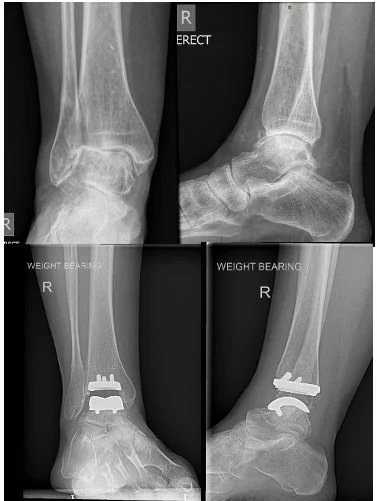

Figure 1: right ankle replacement for end stage osteoarthritis. Pre operative and post-operative Xrays (3 months) shown.